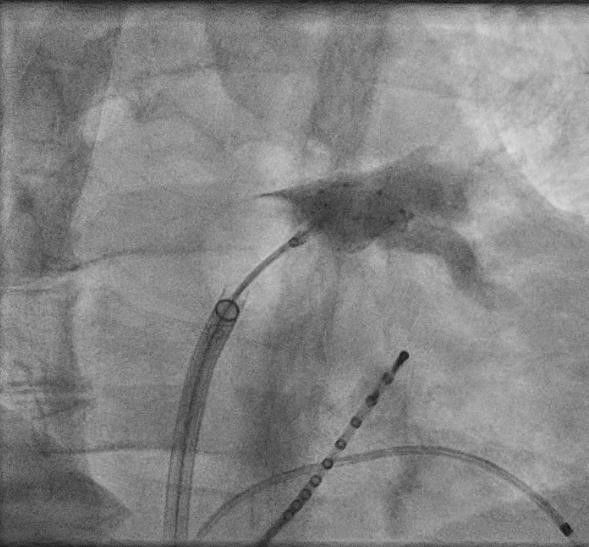

Neben der Gabe von antiarrhythmisch wirksamen Medikamenten besteht die effektivste Behandlung in einer Katheterbehandlung, der sogenannten Pulmonalvenenisolation. Bei der Pulmonalvenenisolation handelt es sich um komplexe Interventionen. Die Erfolgsquote dieses Verfahrens beträgt nach einem Jahr etwa 60-80%, nach einem eventuell notwendigen Zweiteingriff sogar bis zu 90 Prozent.